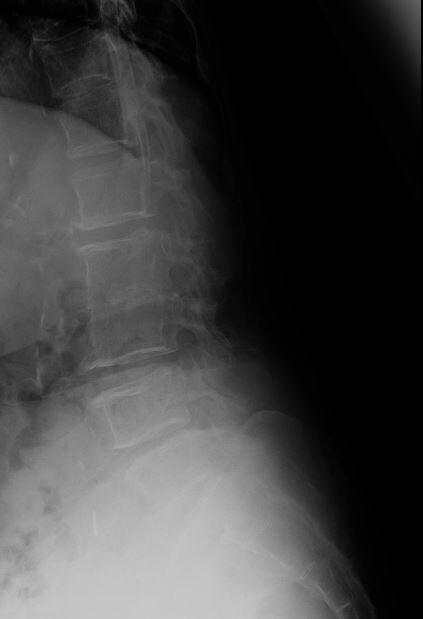

An X-ray of the lumbosacral spine showed narrowing of the L2-L3 disc space following which an MRI of the spine was arranged. Blood cultures were positive for Streptococcus bovis.

The MRI showed degenerative changes at L2-L3, but more importantly, spondylodiscitis at S1-S2, with impingement of nerve roots (which would explain the symptom of buttock pain. This is most plausibly attributed to the Streptococcus bovis bacteremia.